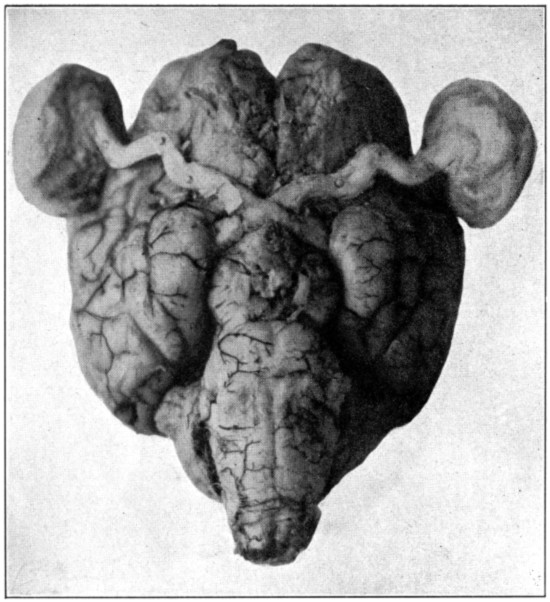

Brain, showing eyes with muscles removed, optic nerves, and chiasm.

| 0. | Brain showing eyes with muscles removed, optic nerves, and chiasm | Frontispiece |